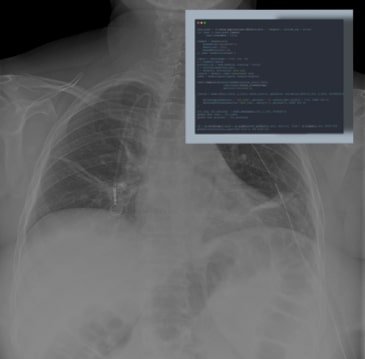

Pneumonia Detection in Chest X-Rays Using Deep Learning

This study applies artificial intelligence to detect pneumonia in chest X-rays.

Posted by buchanle on Tuesday, April 30th, 2024 in May 2024, Artificial Intelligence, Computer Vision, Deep learning, Neural Networks, Pneumonia